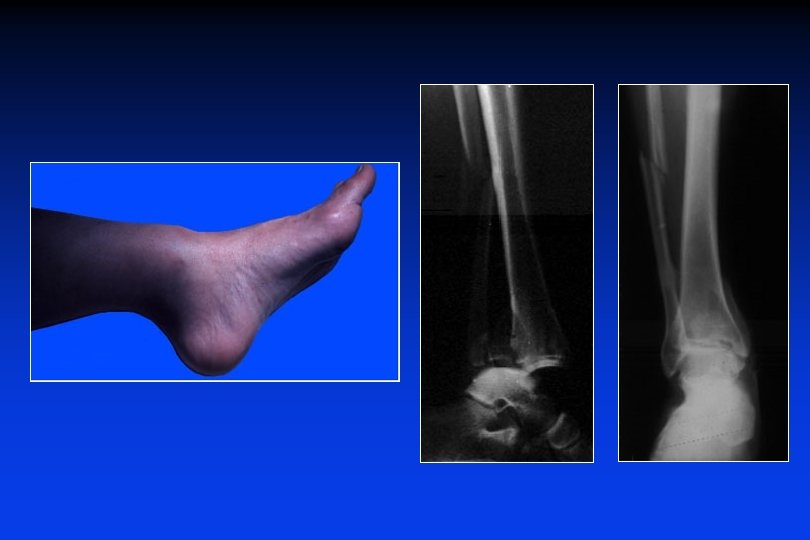

Fratture in flessione dorsale Iperflessione dorsale brutale e compressione verticale - Caduta dall’alto - Incidente stradale: il piede sul pedale del freno L’astragalo sollecita i malleoli che sono fratturati ed il margine anteriore della tibia staccato.

Fratture in flessione dorsale Le fratture marginali anteriori sono totali o parziali A volte, tutto il margine anteriore é fratturato, in blocco o in parecchi frammenti, determinando una sub-lussazione o una lussazione anteriore dell’astragalo in avanti.